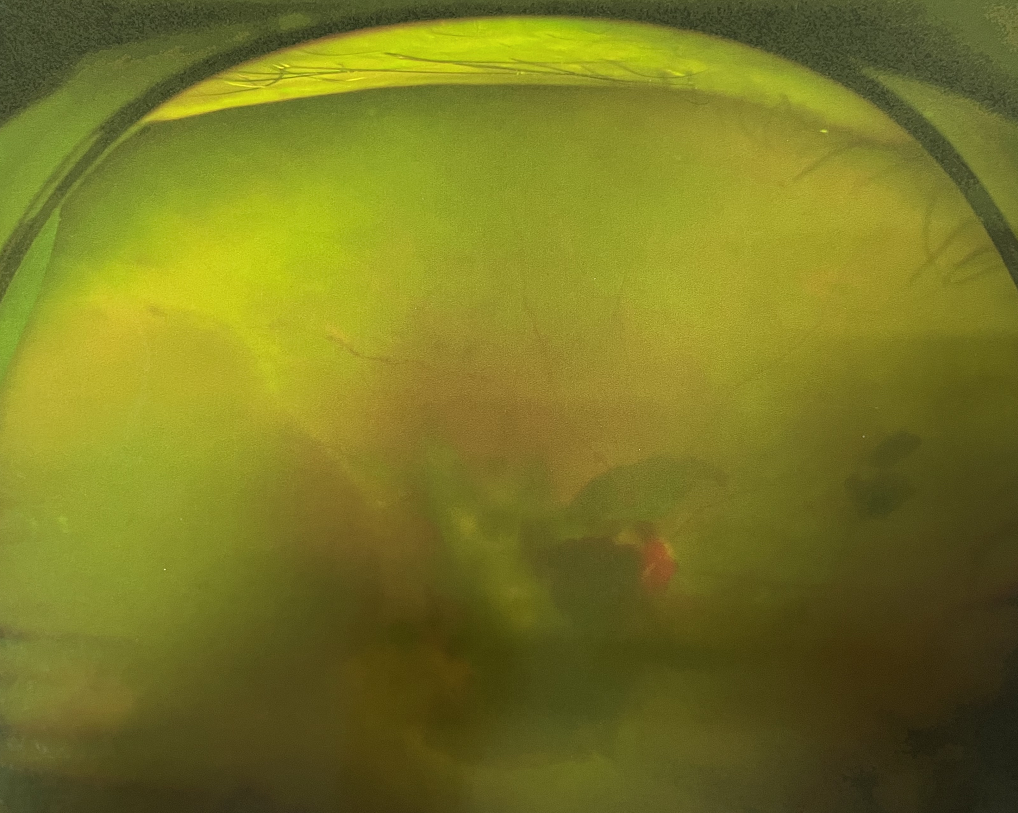

糖尿病視網(wǎng)膜病變是糖尿病在眼部的主要并發(fā)癥,是我國四大致盲眼病之一,主要以視網(wǎng)膜血管改變?yōu)椴±硖卣鳌Q鄣锥啾憩F(xiàn)為視網(wǎng)膜出血、滲出、新生血管及增殖膜形成,嚴重威脅患者的視覺健康。

糖尿病視網(wǎng)膜病變患者早期可能沒有明顯的視力下降,有些患者因為玻璃體出血會出現(xiàn)突然視力下降,晚期患者視力多有明顯下降。

糖尿病視網(wǎng)膜病變可分為六期:

Ⅰ期:有微血管瘤或并有小出血點。

?、蚱冢河悬S白色“硬性滲出”或并有出血斑。

?、笃冢河邪咨?ldquo;軟性滲出”或并有出血斑。

Ⅳ期:眼底有新生血管或并有玻璃體積血。

?、跗冢貉鄣子行律芑虿⒂欣w維膜增生。

Ⅵ期:眼底有新生血管或并有纖維膜增生,并發(fā)視網(wǎng)膜脫離。